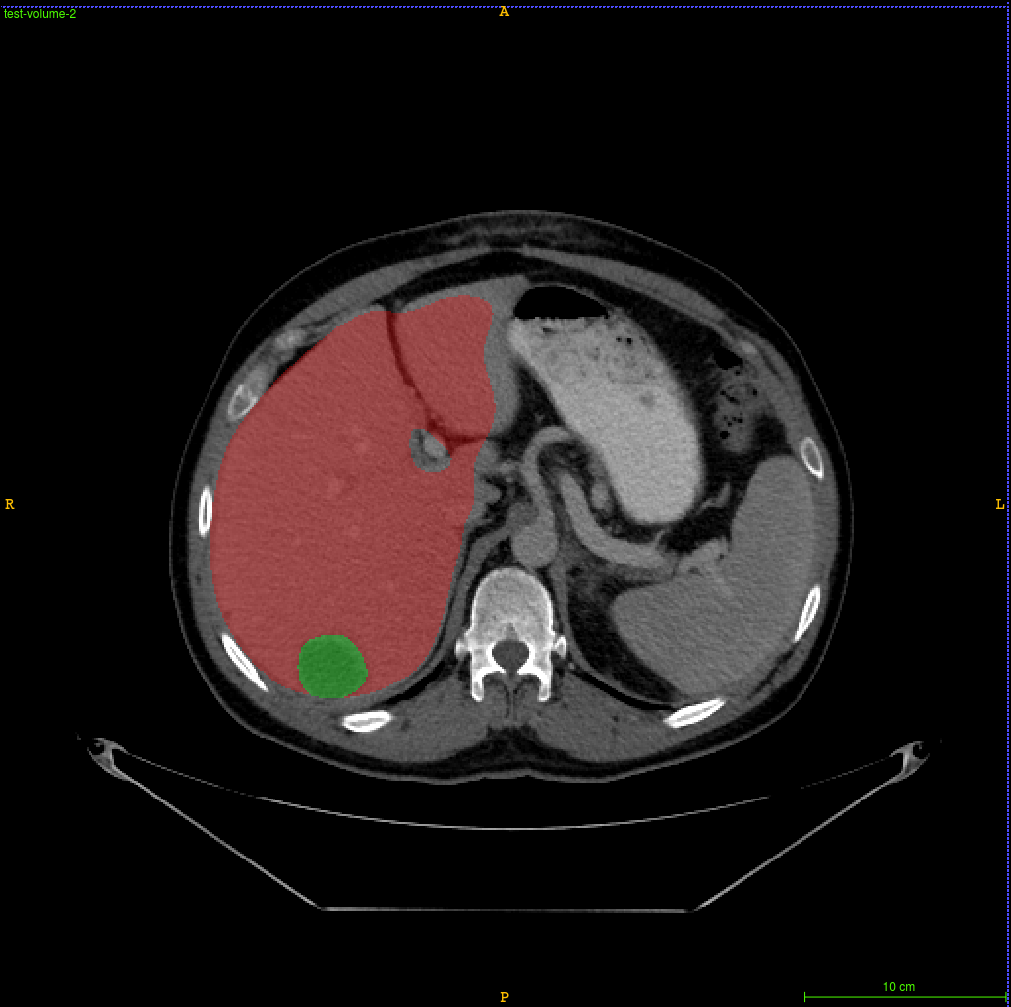

Refer to caption

Figure 3: The figure shows the segmentation results of liver and tumor in a CT slice of test dataset. The color red indicates liver and green indicates tumor. The proposed model sometimes mis classifies darker vessels as tumors.